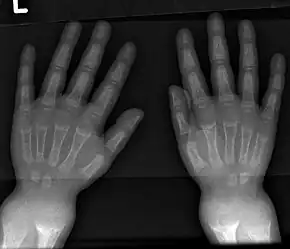

| X-ray of a two-year-old with rickets, with a marked bowing of the femurs and decreased bone density | |

An X-ray or radiograph of an advanced sufferer from rickets tends to present in a classic way: the bowed legs (outward curve of long bone of the legs) and a deformed chest. Changes in the skull also occur causing a distinctive "square headed" appearance known as "caput quadratum".[14] These deformities persist into adult life if not treated. Long-term consequences include permanent curvatures or disfiguration of the long bones, and a curved back.[15]